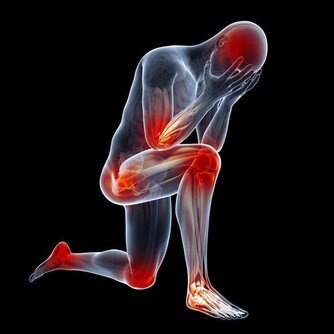

當身體中的濕氣過重時,人就會感覺到全身都不舒服,不是覺得這裡痛,就是那裡酸,沒有辦法專心去做一件事情,會嚴重影響到我們的生活與學習。而且,當身體的濕氣累積到一定程度的時候,身體就會產生各種各樣的毛病。而夏天又是一個濕氣增長的季節,因此,今天我們就來跟大家談一談怎樣趕走我們身體內部的濕氣。